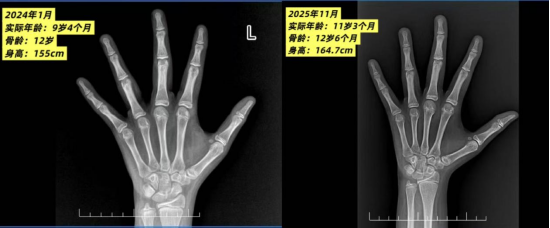

孩子长得快不一定是好事,骨龄才是“真相”

检查发现,婕婕体型偏胖,双乳已经发育到B3期——之前妈妈以为是胖,根本没注意到。更让周医生警觉的是,婕婕这一年的生长速度太快了,这背后可能藏着问题。周医生建议婕婕拍一张左手腕的X光片,看看骨龄。结果出来,让所有人心头一紧:婕婕的骨龄已经是12岁,比她的实际年龄9岁4个月,足足超前了2.7岁!这意味着婕婕虽然现在比同龄人高,但她的骨骼已经“提前成熟”了,骨骺正在加速闭合。就像一棵原本能长五年的树,现在三年就长成了,剩下的两年没机会再长了。根据骨龄预测,婕婕的成年身高只有155cm左右,明显低于父母给她的遗传身高。妈妈听到这个数字,整个人都愣住了。她怎么也没想到,自己一直引以为傲的“长得高”,竟然是孩子在提前透支生长空间。

两年时间过去了。2025年11月,当婕婕再次来到周医生的诊室复查时,数据让人欣慰:实际年龄:11岁3个月,身高:158.1cm,骨龄:12岁6个月。对比一下两年前的数据:骨龄从12岁增长到12岁6个月,两年时间只长了8个月!这意味着,治疗成功地为婕婕的骨龄踩了刹车,把生长周期重新拉回了正轨。更重要的是,预测成年身高从之前的155cm,提升到了164.7cm。虽然离遗传身高还有一点距离,但相比最初的结果,已经多抢回了几乎10厘米。家长和孩子对治疗效果非常满意。妈妈说,如果当初再晚来一步,等到月经规律了、骨龄再跑快一点,可能就真的来不及了。

骨龄是判断孩子生长发育状况的重要指标。尤其是处于3-18岁成长期的孩子,如果身高不理想,或者发育迹象过早出现,拍一张左手腕X光片,看看骨龄是超前还是落后,能帮助家长更清楚地了解孩子还有多少生长空间。